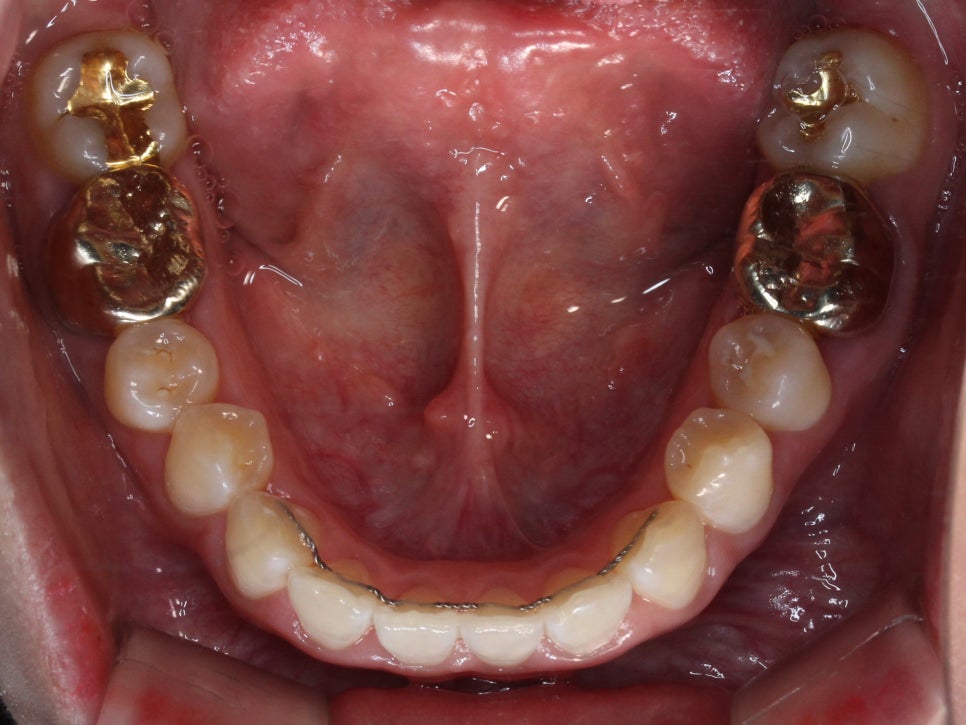

꽤 많이 개선이 되었지만

아직 #12가 배열이 잘 되었다기 보단

그냥 거꾸로 물리던 것이 해소 된 정도입니다.

약간 뻐드러진 느낌과

치축만 조금 더 개선 시키고 마무리 하기로 했습니다.